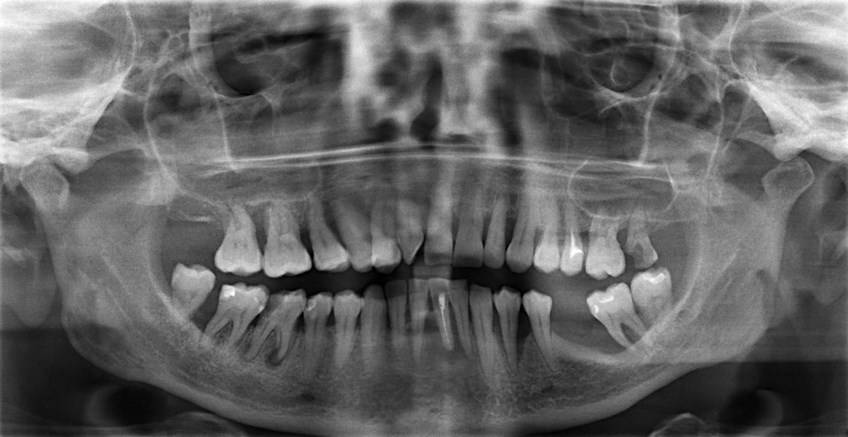

- Ортопантомограмма

Рентген зубов – безопасная процедура для кормящей мамы, которая не оказывает отрицательного влияния на здоровье человека, протекание грудного кормления, состав и объем грудного молока

Рентген важно делать только на современном цифровом оборудовании с минимальным облучением

Теперь давайте вспомним математику и посчитаем то, сколько можно делать человеку рентгеновских снимков. Прицельный снимок одного зуба равен 2-3 микрозивертам. Можно делать в год 300-500 рентгеновских снимков. Панорамный снимок (все зубы) равен 16-18 микрозивертов. Можно делать 60-70 рентгеновских снимков в год.

Теперь разберемся с компьютерной томографией. 1 снимок, сделанный на данном устройстве, равен 60-80 микрозивертов. Можно делать 16-20 рентгеновских снимков в год.